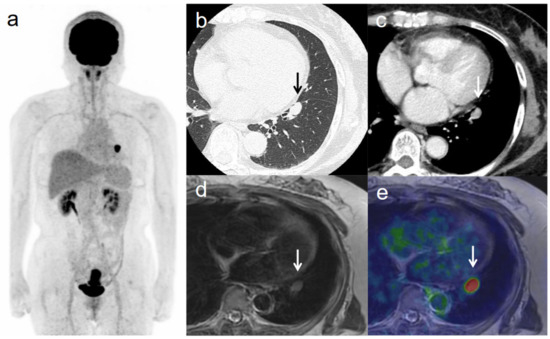

Figure 3. A 53-year-old woman with IVB cervical cancer and pelvic lymph node metastasis. (a) 18F-FDG PET image shows FDG uptake by tumor in the cervical cervix (arrow) and right pelvic and left inguinal lymph nodes. (b) CT shows a right pelvic lymph node of short-axis diameter >1 cm (arrow). (c) Axial T2-weighted PET/MR image shows FDG uptake by the right pelvic lymph node (arrow). This finding is strongly suggestive of pelvic lymph node metastasis, which was confirmed by histopathologic examination. (d) Sagittal T2-weighted PET/MR image shows FDG uptake by the cervical tumor and invasion into the corpus uteri (arrow), which was confirmed by histopathologic examination. (e) Axial T2-weighted PET/MR image shows FDG uptake by the left inguinal lymph node (arrow).

3.3. Revised FIGO Staging